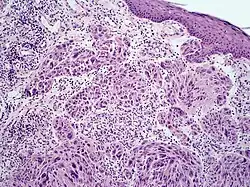

Melanoma with features of a Spitz nevus

Melanoma with features of a Spitz nevus, also known as a Spitzoid melanoma, is a cutaneous condition characterized histologically with tissue similar to a spitz nevus and with overall symmetry and a dermal nodule of epithelioid melanocytes that do not mature with progressively deeper dermal extension.[1]